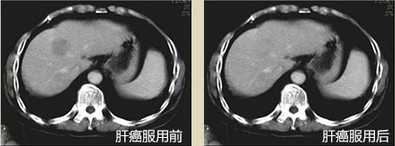

• 放化疗不再痛苦,活着有奔头...山东,胡先生,62岁,肝癌早期 3年前我不幸诊断为干细胞病变早期,手术后,出现食欲不佳,恶心呕吐。腹胀便频等现象。手术效果也不明显,伤口生长缓慢,非常痛苦,服用灵芝孢粉产品10天后便有反应,化疗症状开始好转,28天后伤口愈合,疼痛也减轻了。整个人的精气神都极大改善,之后一直坚持服用灵芝孢粉,2年了,我依旧健康的活着。